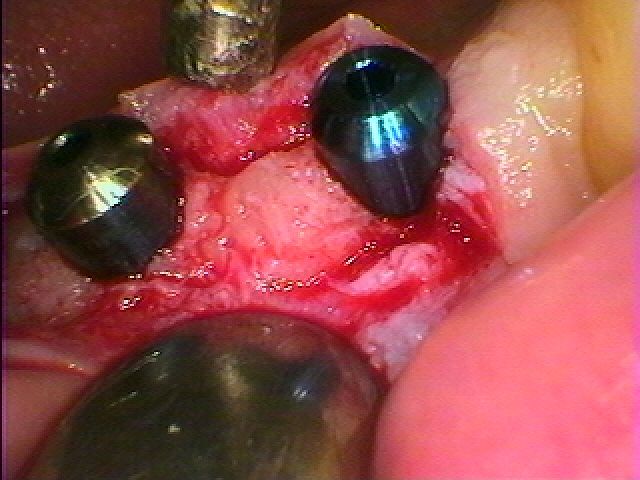

欠損部にはこのようにインプラントを埋入しています

埋入後になります

コーティング面がしっかりと隠れるように埋入しています